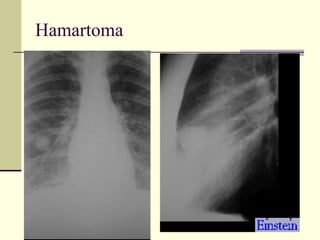

Solitary Pulmonary Nodule   1. Bronchogenic ca  2. Hamartoma  3. Histoplasmoma  4. TB granuloma  5. Bronchial adenoma 6. Solitary met  7. Round pneumonia  8. Rounded atelectasis

Hamartoma